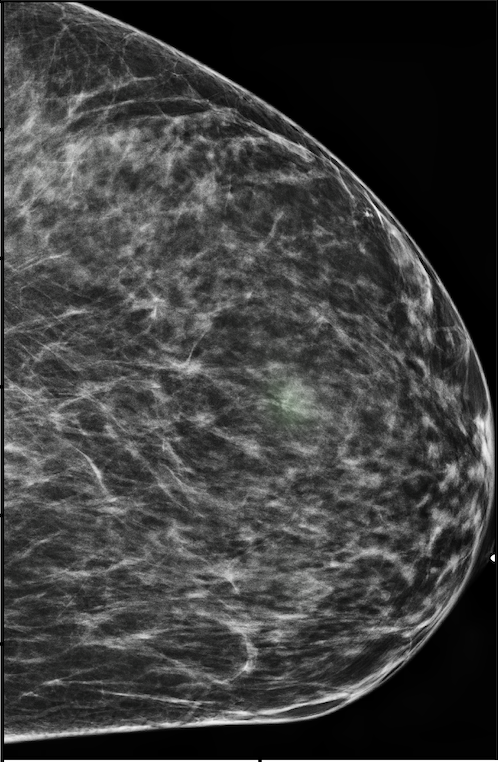

The NYU Breast Cancer Screening Dataset [78] includes 229,426 exams (1,001,093 images) from 141,472 patients.222Our retrospective study was approved by our institutional review board and was compliant with the Health Insurance Portability and Accountability Act. Informed consent was waived. Each exam contains at least four images which correspond to the four standard views used in screening mammography: R-CC (right craniocaudal), L-CC (left craniocaudal), R-MLO (right mediolateral oblique) and L-MLO (left mediolateral oblique). An example is shown in Figure 3.

Across the entire dataset (458,852 breasts), malignant findings were present in 985 breasts () and benign findings in 5,556 breasts (). All findings are confirmed by at least one biopsy performed within 120 days of the screening mammogram. For the remaining screening exams that were not matched with a biopsy, we assigned labels corresponding to the absence of malignant and benign findings in both breasts. In each exam, the two views of the same breast share the same label.

For all exams matched with biopsies, we asked a group of radiologists (provided with the corresponding pathology reports) to retrospectively indicate the location of the biopsied lesions. This way we obtained the segmentation labels: where if pixel belongs to the benign/malignant findings. An example of such a segmentation is shown in Figure 3. In all experiments (except for experiments in Section 3.6 that assess the benefits of utilizing segmentation labels), segmentation labels are only used for evaluation. We found that, according to the radiologists, approximately of exams were mammographically occult, i.e., the lesions that were biopsied were not visible on mammography, even retrospectively, and were identified using other imaging modalities: ultrasound or MRI.